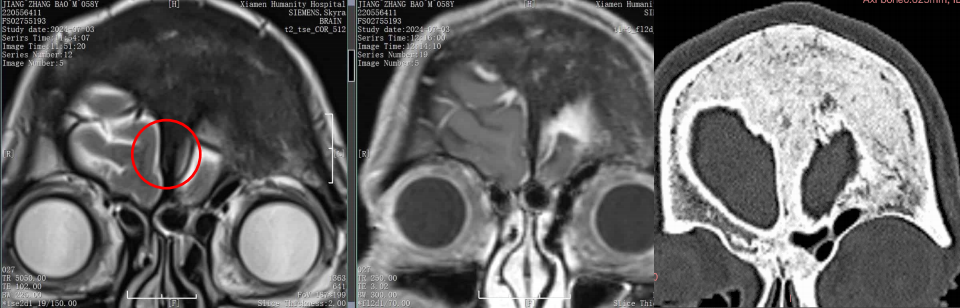

MRI

影像重建

腫瘤與靜脈、矢狀竇的關系

靜脈影像重建

CT重建

左額內外板可見骨質增生

■ 初步診斷:左額部凸面-矢狀竇旁腦膜瘤